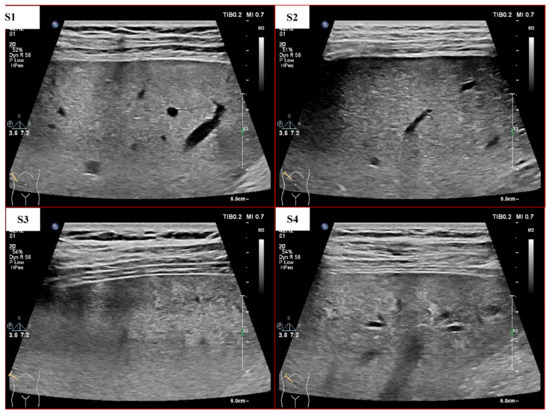

Although many LF staging methods based on machine learning (ML) have been proposed, the automated grading of LF remains challenging due to the slight texture differences between different LF stages, as shown in Figure 1. In addition, the quality of US images is strongly influenced by equipment performance, operator skills, noise and individual differences between patients [15]. Therefore, the performance of automated diagnosis methods still needs to be improved.

Figure 1.

US images with different degrees of LF (S1–S4 means liver fibrosis stages 1–4, which are determined through liver biopsy by pathologists).